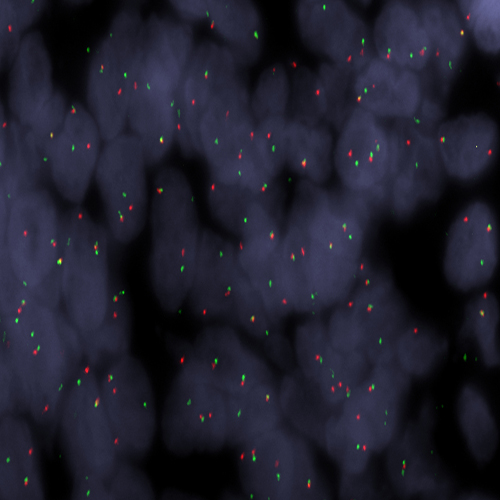

Synovial Sarcoma stained using SS18 (18q11) Break – XL for BOND (KBI-XL018).

The SS18 (18q11) Break - XL for BOND FISH probe detects genomic translocations involving the SS18 gene. SS18 (18q11) Proximal - XL and SS18 (18q11) Distal - XL are optimized to detect genomic regions proximal and distal to break points in the SS18 gene region.

When combined, both probes are used to detect translocations involving the SS18 gene at 18q11.